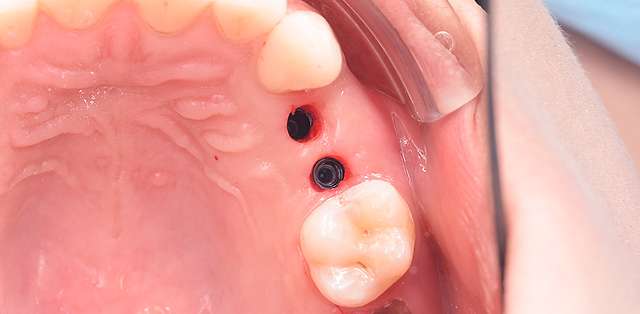

Chirurgia ghidata, ne faciliteaza o pozitie ideal pre-planificata, care nu tine cont doar de os, ci si de o pozitie optima in relatie cu viitorul dinte.Chirurgia ghidata înseamnă o precizie crescuta, care inseamna siguranta mai mare, timp operator mai scazut, si trauma mai mica. De asemenea focusul in acest tip de interventii a migrat spre reconstructia tesuturilor, care e pe termen lung are un impact mult mai mare atat estetic cat si biologic, inserarea implantului in sine fiind trivializata de folosirea ghidului chirurgical. Cazul de fata este un exemplu al acestui tip de abordare.